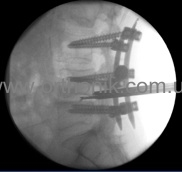

Spondylodesis

This is an operation in which the surgeon connects two (or more) vertebrae, preventing them from further displacement. In some cases, patients suffering from spinal stenosis, together with spondylodesis, are given a decompression laminectomy whose purpose is to fix those parts of the spine in which vertebral displacement or separation has been recorded. Such fixation can help reduce the intensity of pain, improve the patient's performance and general condition.